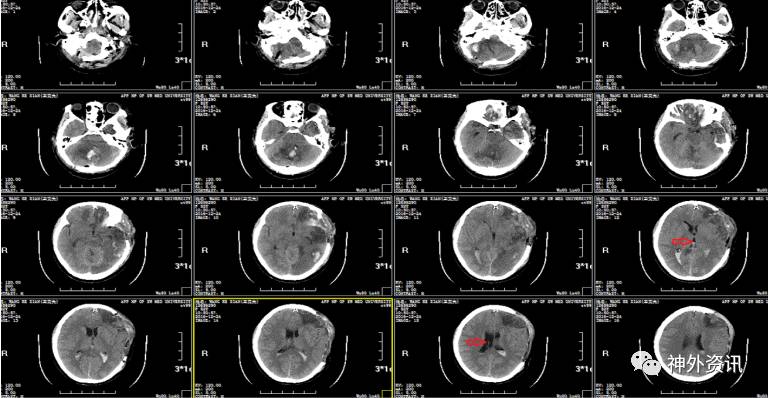

辅助检查:入院头颅CT示:①左侧额颞顶部硬膜下血肿;右侧枕部硬膜外血肿;左侧额颞叶及右侧小脑半球多发挫裂伤伴血肿形成;蛛网膜下腔积血;大脑镰下疝。②枕骨右侧骨折;蝶窦后壁骨折,累及枕骨斜坡;蝶窦右侧积液/积血,鞍区少许积气;枕部头皮肿胀。

初步诊断:重型内开放性颅脑损伤:①左额颞及右小脑半球脑挫裂伤伴血肿,②左额颞顶枕部急性硬膜下血肿,③左额部硬膜外血肿,④颅底骨折,⑤右枕骨骨折,⑥左颞部头皮血肿

空心箭头:小脑血肿,约2cm*2cm*2cm;实心箭头:左额叶脑挫裂伤伴硬膜外血肿

手术指征:患者意识浅昏迷,双瞳不等大,头颅CT示:多发脑挫裂伤、急性硬膜下/外血肿,环池不清。

2016.12.20:术后第1天,患者意识仍昏迷,自主呼吸尚可,出现双瞳不等大,左瞳3.0mm,右瞳2.0mm,光反射消失,复查头颅CT发现,原小脑挫裂伤灶出血明显增加,周围水肿明显,环池仍不清。

小脑血肿增加:约4.6cm*5.1cm*2cm